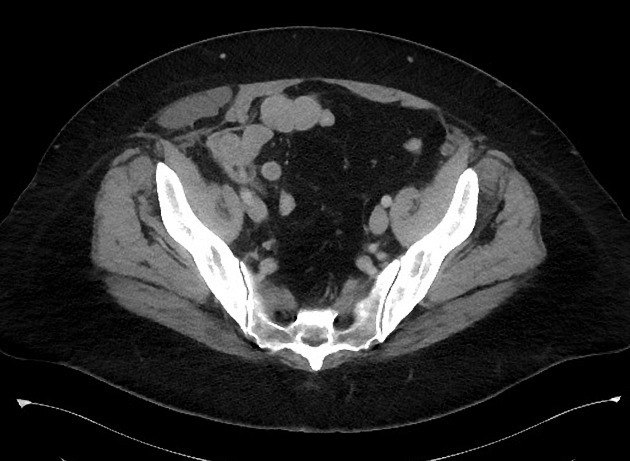

Thoát vị thành bụng

» Thông tin: Nữ giới – 50 tuổi.

» Lâm sàng: Đau hố chậu phải.